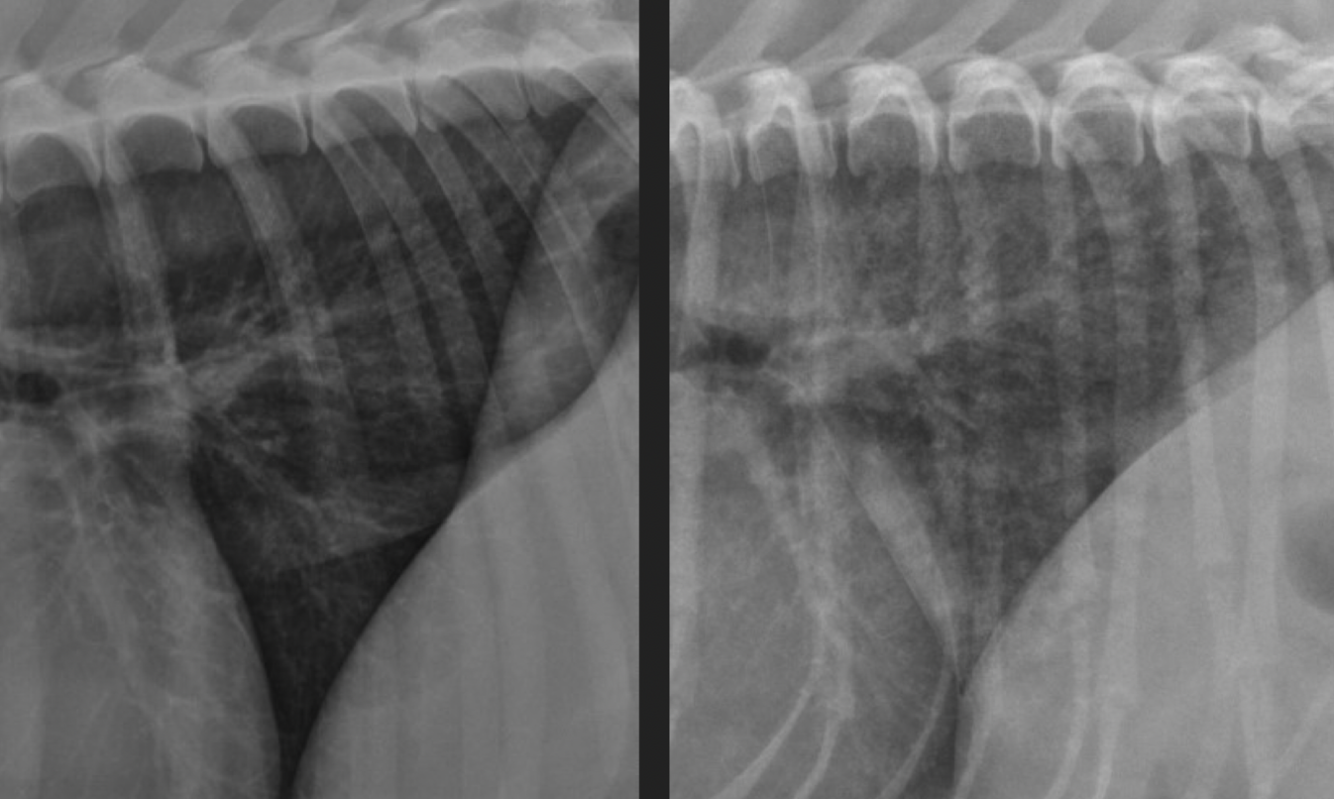

what kind of pattern

normal- left

interstitial- right